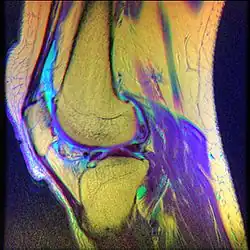

Diagnostic methodMRI

Chondromalacia patellae (also known as CMP) is an inflammation of the underside of the patella and softening of the cartilage.

• Magnetic Resonance Imaging (MRI) – to observe cartilage condition and assess deterioration